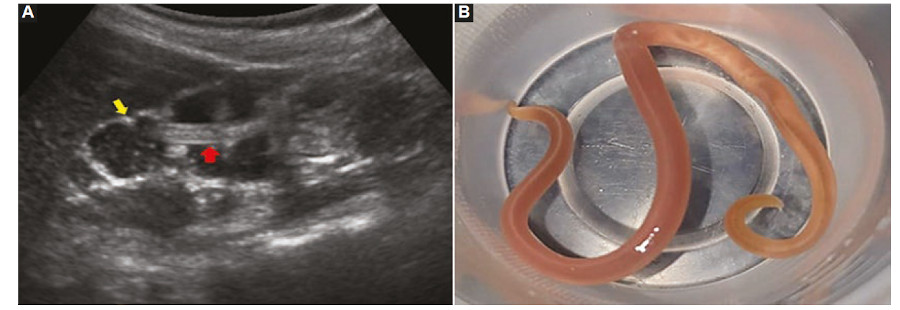

- Caso 1. Corresponde a una niña de cuatro años de edad que consulta por dolor abdominal difuso, diarrea, náuseas y vómitos, y fiebre no registrable de

12 horas de evolución, sin otros antecedentes de relevancia. Ante la sospecha de suboclusión intestinal se le solicita una ecografía abdominal (Fig. 1).

En la ecografía se identifican signos particulares como el de la “masa de gusanos” y del “doble tubo”. Este último hace referencia a la visualización intestinal intraluminal de dos líneas ecogénicas externas y otras dos internas de similares características con un área central hipoecogénica que representa el tracto gastrointestinal del parásito (Figs. 1A y 2 A y C); esta misma imagen vista en corte transversal conforma el “signo del ojo de buey” (Fig. 2 B y D). Se menciona como hallazgo adicional frecuente y de ayuda diagnóstica el desplazamiento del parásito mediante movimientos peristálticos y de ondulación durante la realización del estudio.

El diagnóstico definitivo se efectúa con el laboratorio por la identificación en heces de los huevos de los áscaris o la observación de lombrices adultas en las heces identificadas por el propio hospedero, como en el presente caso 1.